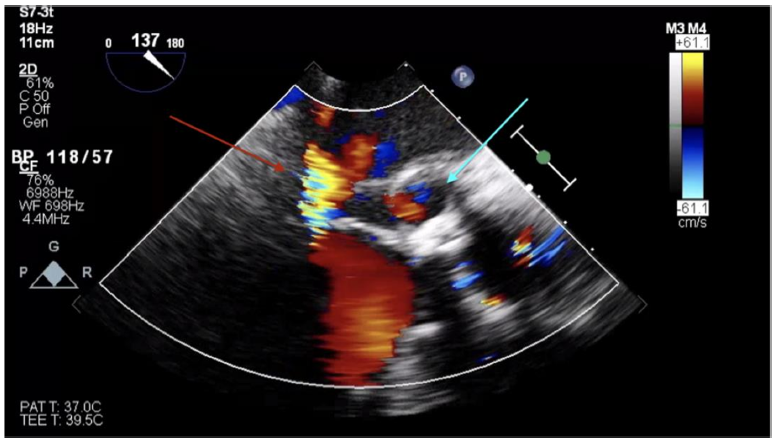

Transthoracic echocardiogram (TTE) showed a left ventricular ejection fraction of 30–35%. Transesophageal echocardiogram (TEE) revealed a mild-to-moderate anterior paravalvular leak of the bioprosthetic AVR and a pseudoaneurysm of the mitral-aortic intervalvular fibrosa (MAIVF) with communication to the left ventricle (Figures 1 and 2). No paravalvular leak had been identified on echocardiograms following his most recent AVR, and there was no evidence of pseudoaneurysm or paravalvular leak on prior TTEs or TEEs. The exact dimensions of the pseudoaneurysm were not documented in the report.